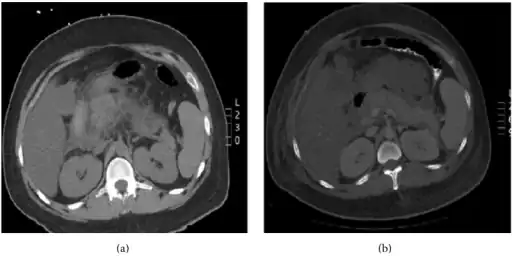

Pegaspargase induced hypertriglyceridemia a) Enlarged pancreas with peripancreatic inflammation b) Interval worsening of acute pancreatitis -